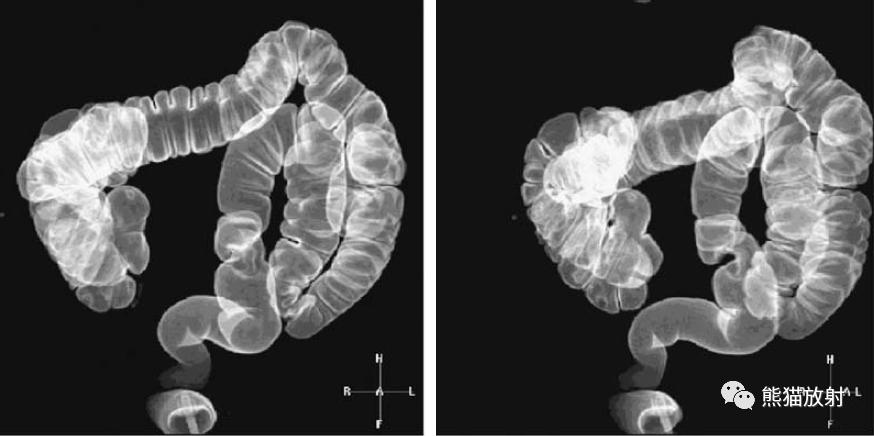

计算机辅助息肉检测。静脉注射造影剂后局灶性肿瘤灌注增加,以自动“检测”潜在的肿瘤(箭头)。